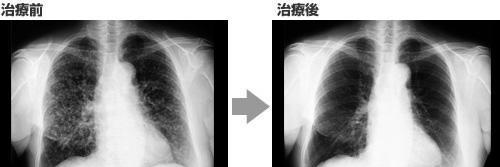

案例1:肺癌

双侧肺发生大大小小的病变的肺腺癌

抗癌剂和高度活性化NK细胞疗法*管双**齐下,结节基本消失!

高度活性化NK细胞疗法完美地完成他的使命!

75岁 女性

在2015年7月被确诊为【肺癌(肺腺癌)】。

能看出双侧肺部存在大量大大小小的结节,不适用于手术和放疗。

只适用于抗癌剂治疗。

因13年前有过乳腺癌病史,加上这次只用抗癌剂的话,患者比较担心其治疗效果,因此在2015年8月开始并用抗癌剂治疗和高度活性化NK细胞疗法。

每两周进行一次高度活性化NK细胞治疗。

首次进行抗癌剂静脉滴注时,由于副作用大,患者身体上、精神上都很痛苦。

第二次开始,以口服抗癌药易瑞沙代替静脉滴注,没有副作用,安稳地度过日常生活。

治疗开始前的肿瘤标志物是:

细胞角蛋白:5.6(正常值2.0ng/ml以下)、NSE·CA15-3为正常值以内。

高度活性化NK细胞疗法5次治疗后的肿瘤标志物是:

细胞角蛋白:1.0,比正常值低,NSE·CA15-3都在正常值以内,比以前更低了。

高度活性化NK细胞疗法11次治疗后的肿瘤标志物是:

细胞角蛋白:0.5,NSE·CA15-3全部都在正常值以内,甚至更低了。

影像检查情况:

进行3次高度活性化NK细胞治疗后,主要肿瘤有缩小趋势,多发结节也逐渐消失。

进行12次高度活性化NK细胞治疗后,主要肿瘤消失,双侧多发结节也基本消失。

此疗法没有像抗癌剂那样的副作用,能够正常生活,这针对患者来说,无疑是最好的治疗。

该患者在2016年2月暂停使用高度活性化NK细胞疗法,继续使用抗癌剂治疗。